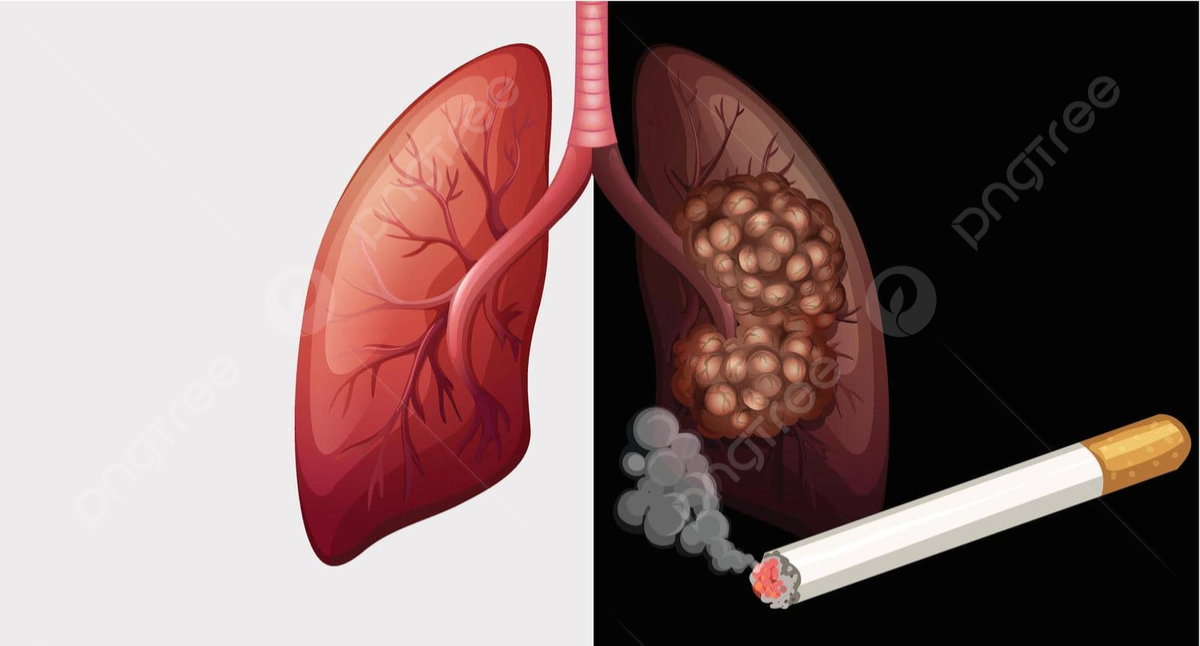

Kasus kanker paru banyak ditemukan di Indonesia. Salah satu penyebab kanker paru karena adanya perokok aktif dan perokok pasif.

"Kanker paru juga termasuk kanker yang banyak di Indonesia, karena perokok aktif dan pasif kita. Untuk mencegah kanker paru, ada program kita, UBM (Usaha Berhenti Merokok)," kata Edi Satriawan, Jumat (12/9).